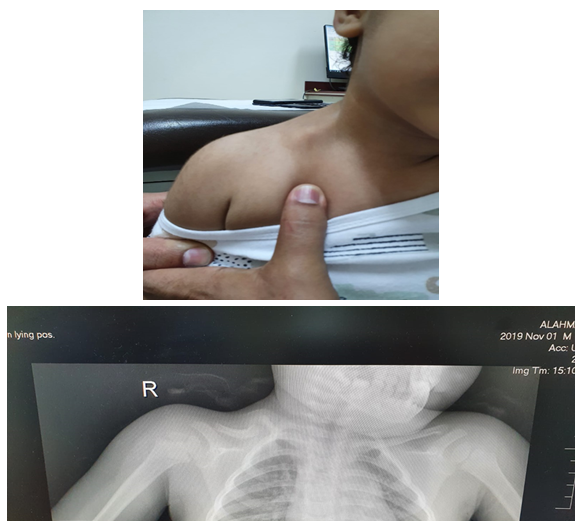

Comminuted Scapular Body Fracture after Seizure

Abdulmohsen Hamad Hamed Alhamyani, Mokhtar Ahmed Alsayed

International Journal of Innovative Research in Medical Science·August 10, 2022